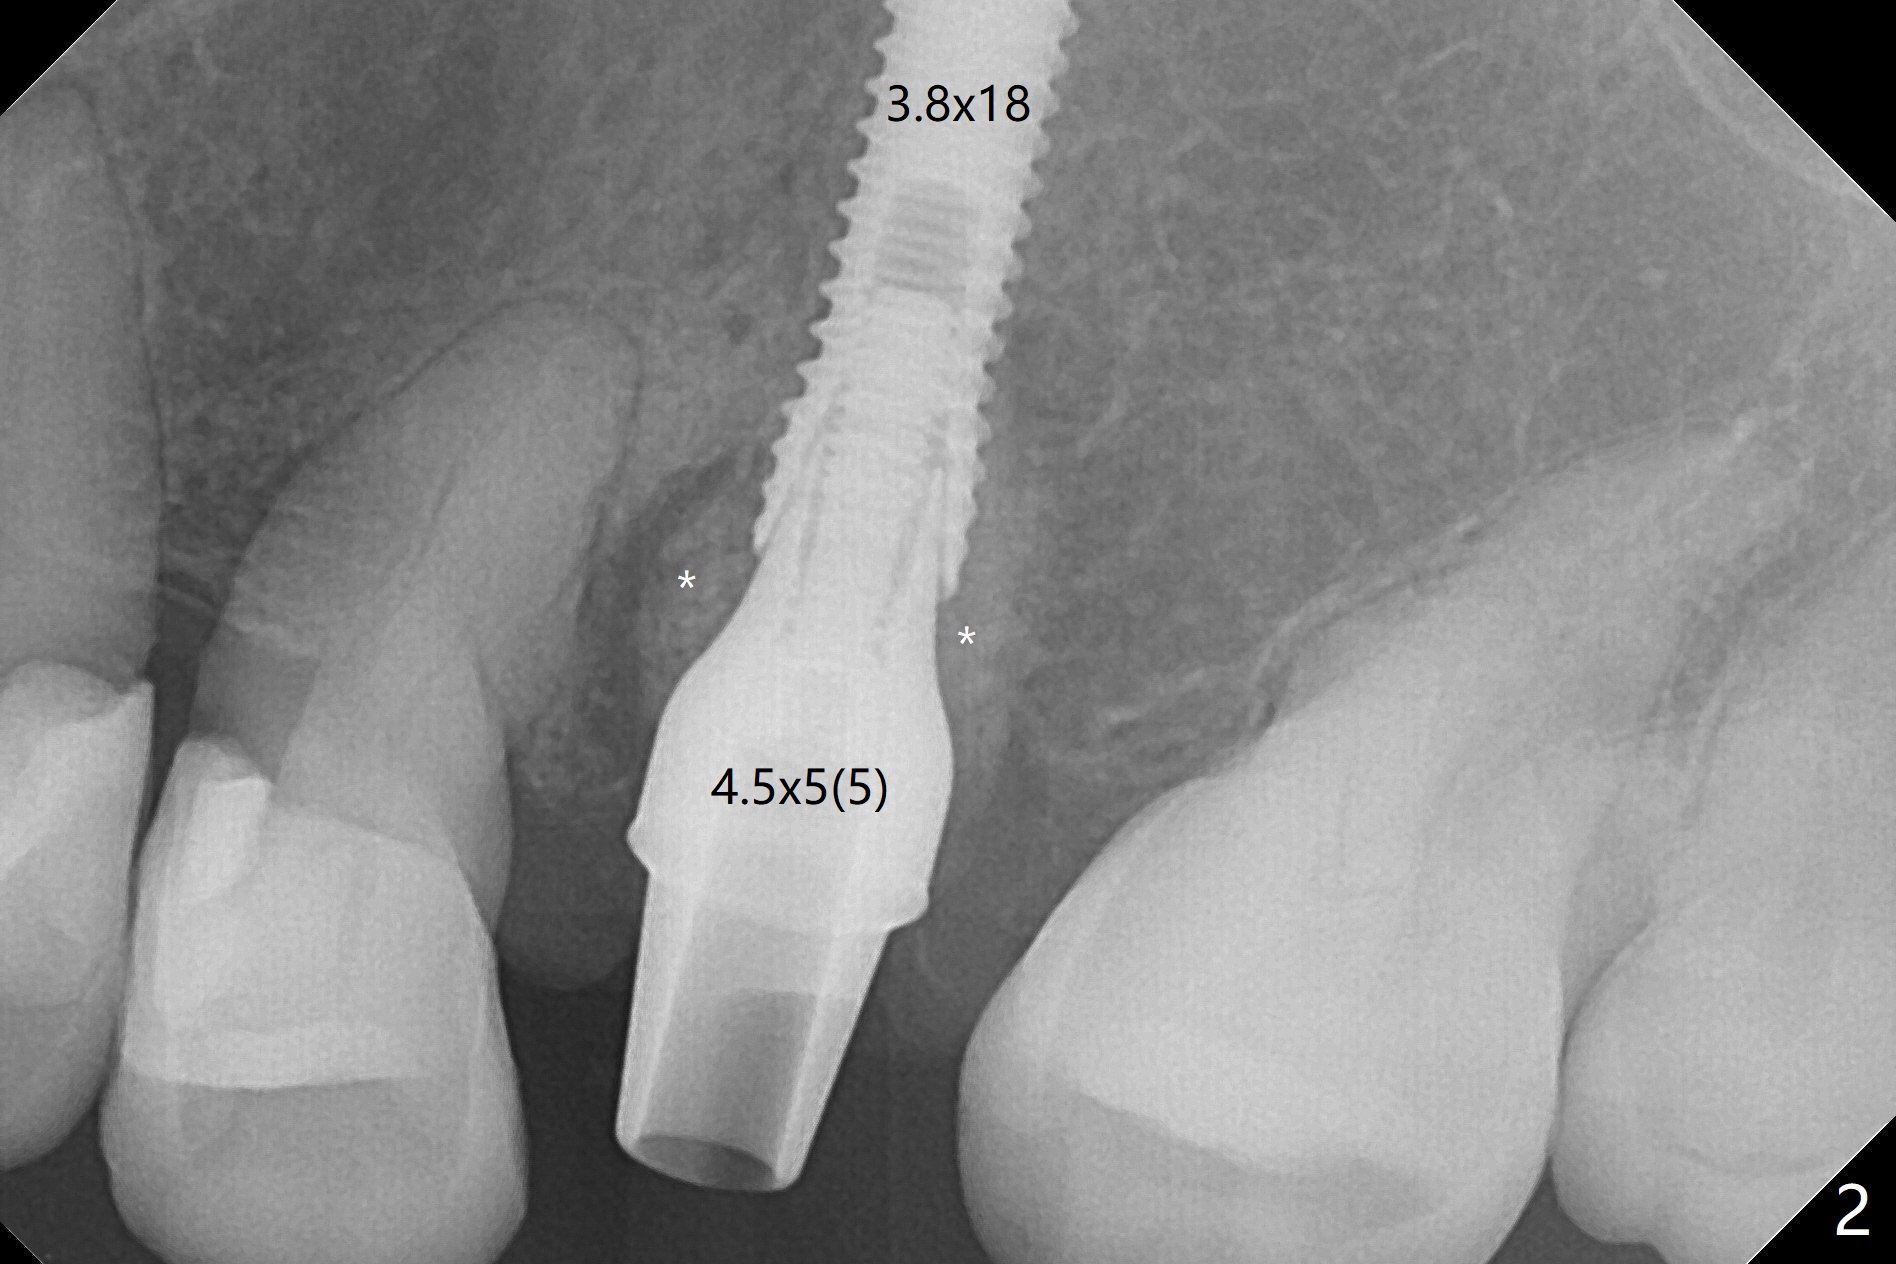

When a 2x16 mm parallel pin is inserted at #13 after extraction, PA does not show the upper end, as related to the long bone (Fig.1). In spite of underprep osteotomy, a 3.8x18 mm implant achieves ~ 20 Ncm of insertion torque (Fig.2). The long implant is still in the lower half of the triangular (cone-shaped) bone (Fig.3 red dashed line) between the nasal cavity (N) and the maxillary sinus (S). The bone is also wide. When a 4.5x5(5) mm abutment is placed, it is buccal. It appears that an angled abutment is needed for final restoration (probably 4.5x15 or 25 degrees, 5 mm cuff). When an angled abutment is placed 1 month posotp, the implant is found unstable. A healing abutment is placed (5.5x7 mm). Progressive loading is initiated 4-5 months postop. The implant becomes stable nearly 5 months postop (Fig.4), but the buccal gingiva is erythematous and tender, probably due to infected bone graft (one large piece), which is removed. One week later, the gingiva looks normal; impression is taken (Fig.5).